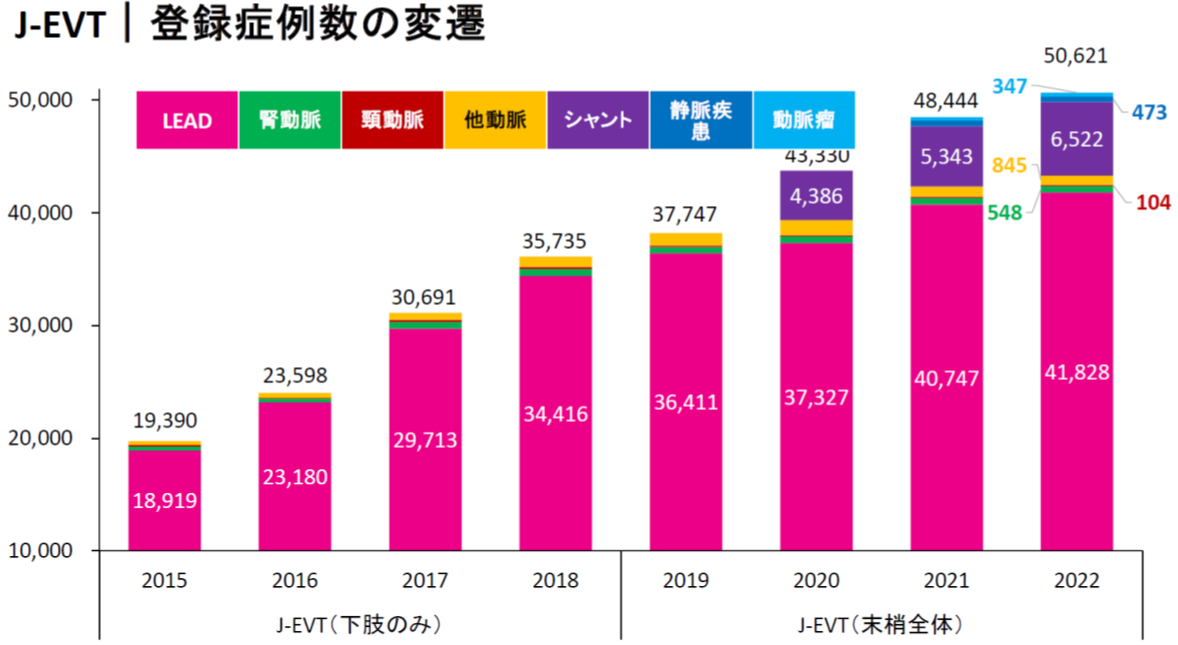

下肢閉塞性動脈硬化症とは

糖尿病、高血圧、脂質異常症といった生活習慣病は全身の動脈硬化を促進して脳梗塞や心筋梗塞発症の危険性を高めます。足に向かう動脈が動脈硬化を起こして血流不足となった結果、さまざまな症状を引き起こす病気が下肢閉塞性動脈硬化症です。末梢動脈疾患は以前ASO(arteriosclerosis obliterans)と呼ばれていましたが、近年ではPAD(peripheral arterial disease)と呼ばれます。またその大部分を占める下肢閉塞性動脈硬化症はLEAD(lower extremity artery disease)と表記されます。生活習慣や高齢化の進行に伴いLEADに対する治療は日本で増加傾向にあります(図1)。

図1:日本心血管インターベンション学会

J-EVT年次報告より引用